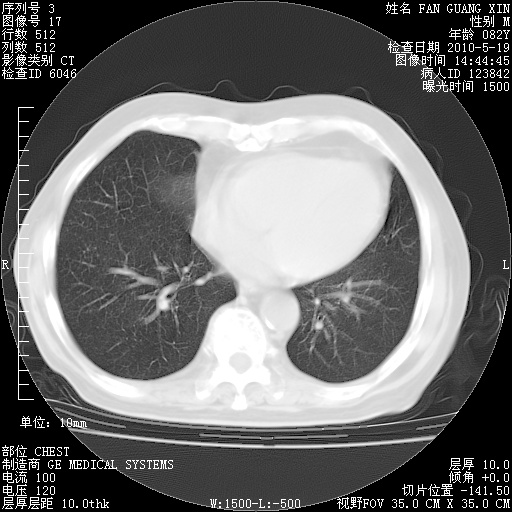

可改为口服强的松40-50mg/d治疗,若病情仍稳定,胸部阴影不再吸收可逐渐减量